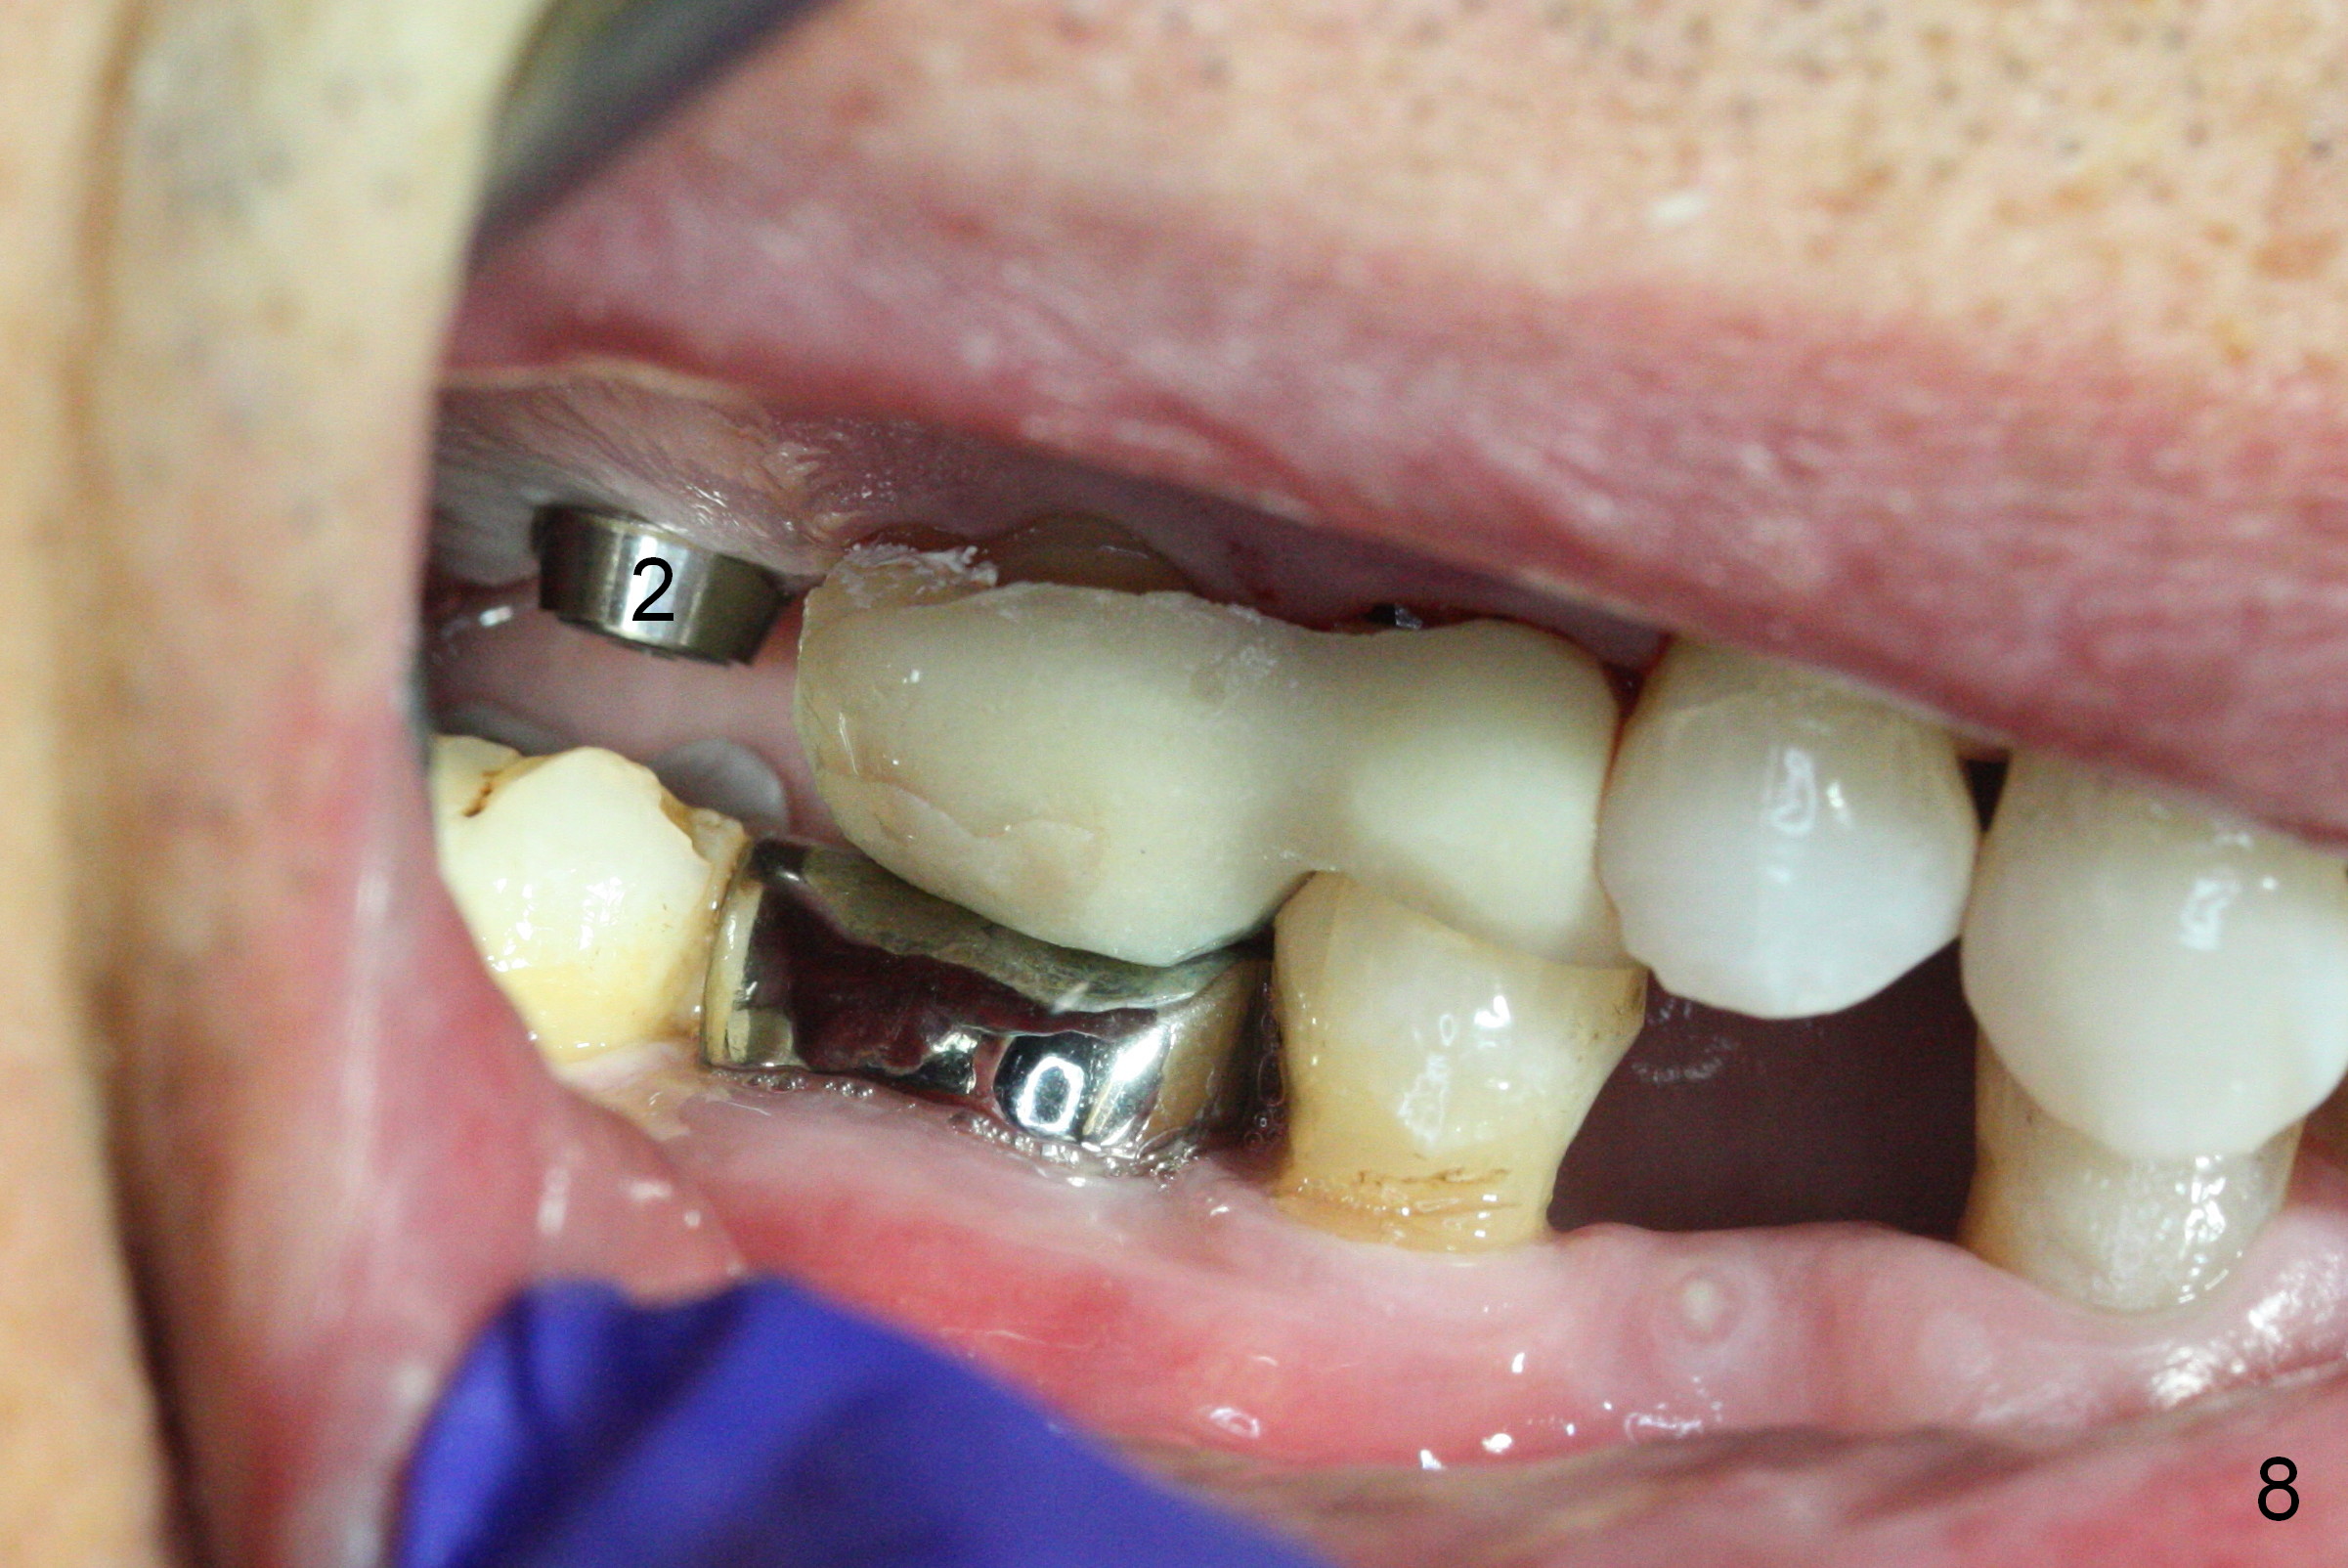

Preop exam shows posterior occlusal collapse (Fig.1) with #3 lost crown and #4 residual root. There is no ridge atrophy at #2 buccopalatally (Fig.2). The root stump of the tooth #4 is oblong, apparently consisting of 2 roots (Fig.3). There is a pointed septum at #4 socket (Fig.4, severe palatal wear of the anterior teeth (^)). After the septum is flattened with surgical handpiece and #8 round bur, 1.6 mm drill is used to start osteotomy in the septum, followed by Magic Drills (MD) and Magic Expanders (ME) alternatively. Osteotomy at #2 is initiated with Magic split, followed by MD and ME in the same manner. Dummy implants are tried in (Fig.5). Because of limited vertical height, Magicore (5.5x9(1) mm) is placed at #2, while a 4x13 mm FC implant 1-2 mm deeper than usual at #4 (Fig.6, ~ 55 Ncm). When a 5x4(2) mm pair abutment is placed at #4, there is no clearance between the Magicore at #2 and the abutment and the opposing dentition. A splinted provisional is fabricated at #3 and 4 to increase the posterior vertical height (Fig.7 P,8). In fact the occlusal contact is confined to the portion of the provisional at #3. The provisional has to extend to #4 to keep bone graft (Fig.6 *) and collagen plug in place. Liquid food is recommended at least 2-3 weeks, since there is no functional occlusal contact on the left. When the wound heals at #4 approximately 2-3 weeks, the splinted provisional can be sectioned with removal the portion at #4 to reduce micro-movement. By the evening the patient is doing well without nasal hemorrhage (sinus lift at #2 (Fig.6 *) or TMJ disturbance (due to increased vertical height).